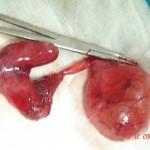

Torsion of Left Undescended Testis (Pre operative and Operative Photo)

Torsion Testis (Pre and Per operative photo)